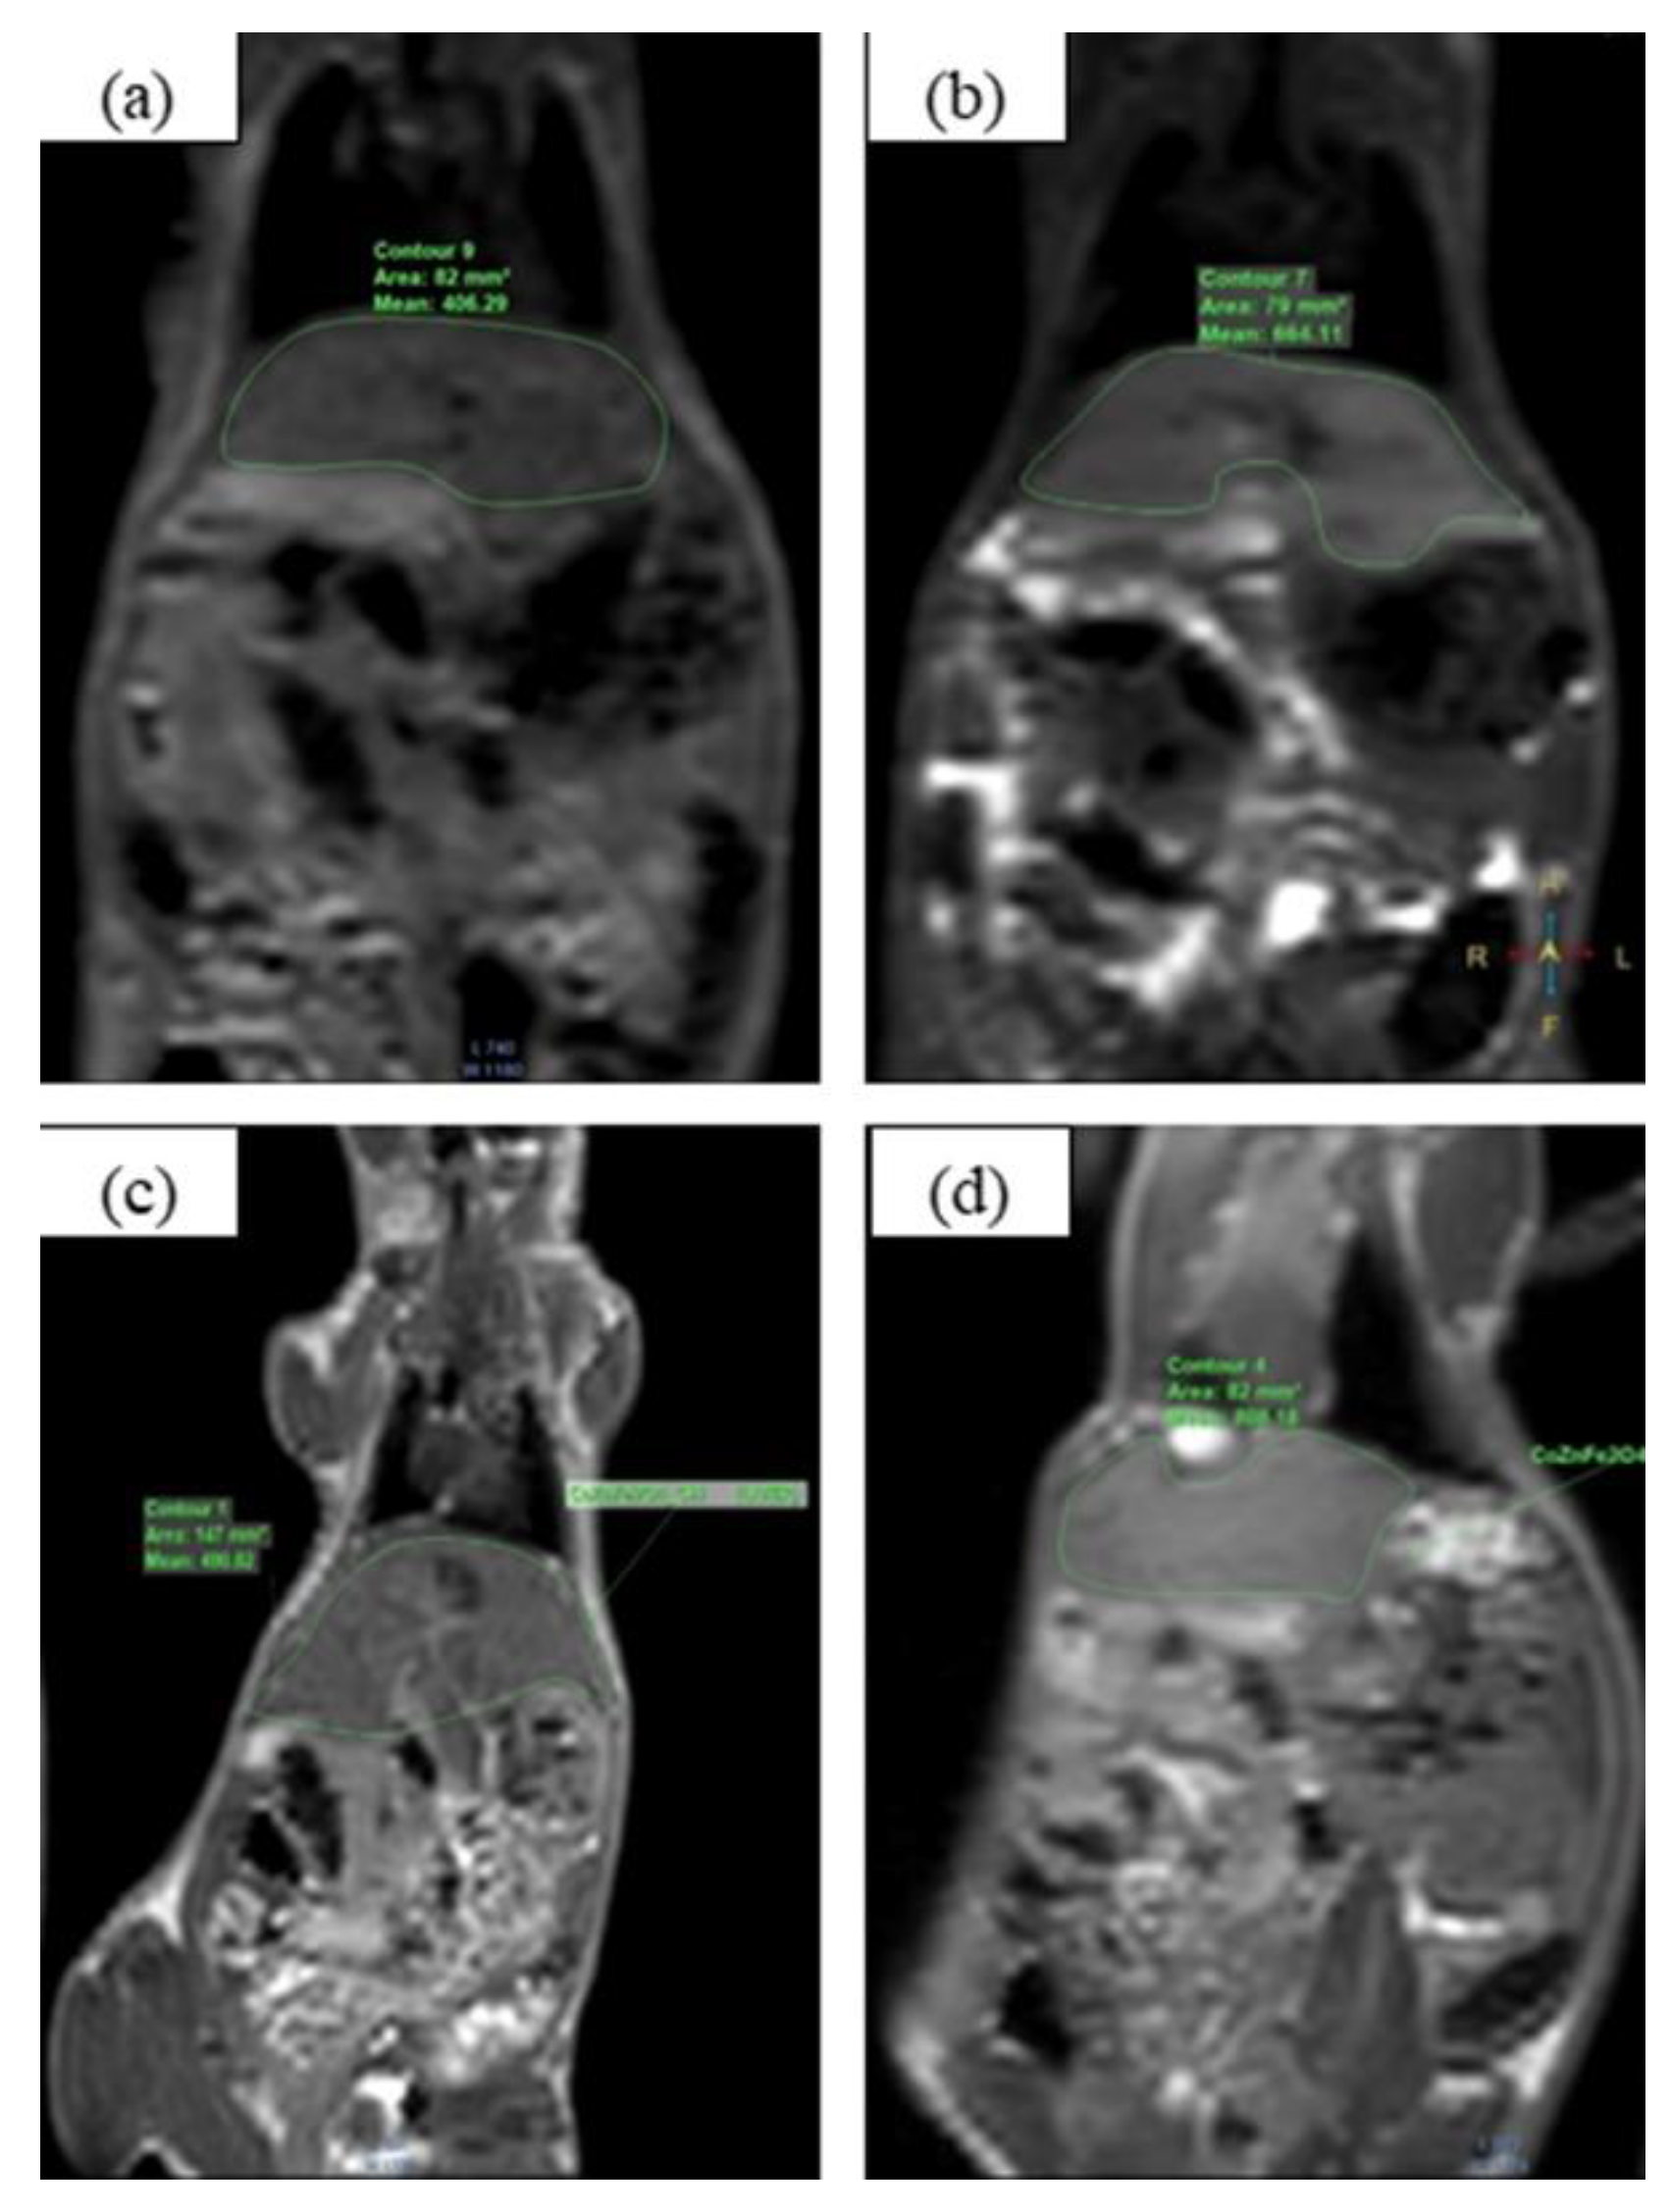

3.3. MRI Application